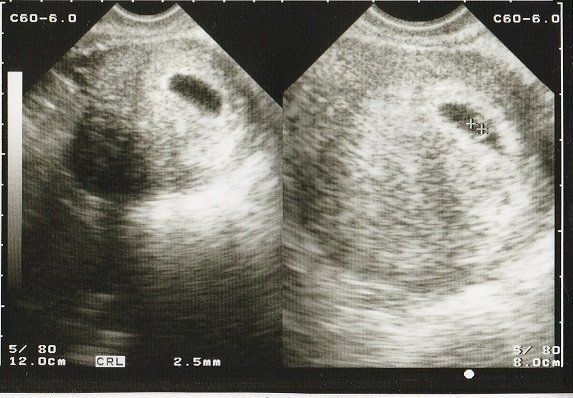

妊娠4週目 初めてのエコー画像

結婚10年目にしてやってきた待望の赤ちゃん。初めてのエコー画像は「ここに本当に赤ちゃんがいるの?」というようなものでした。初期の流産を経験しているので、「何かあったらすぐに連絡するように」と、当時は主治医の先生の携帯番号がエコー写真の下に添えてありました。

妊娠5週目のエコー写真 胎嚢が見える

胎嚢(赤ちゃんがはいった袋)が確認できるようになりました。